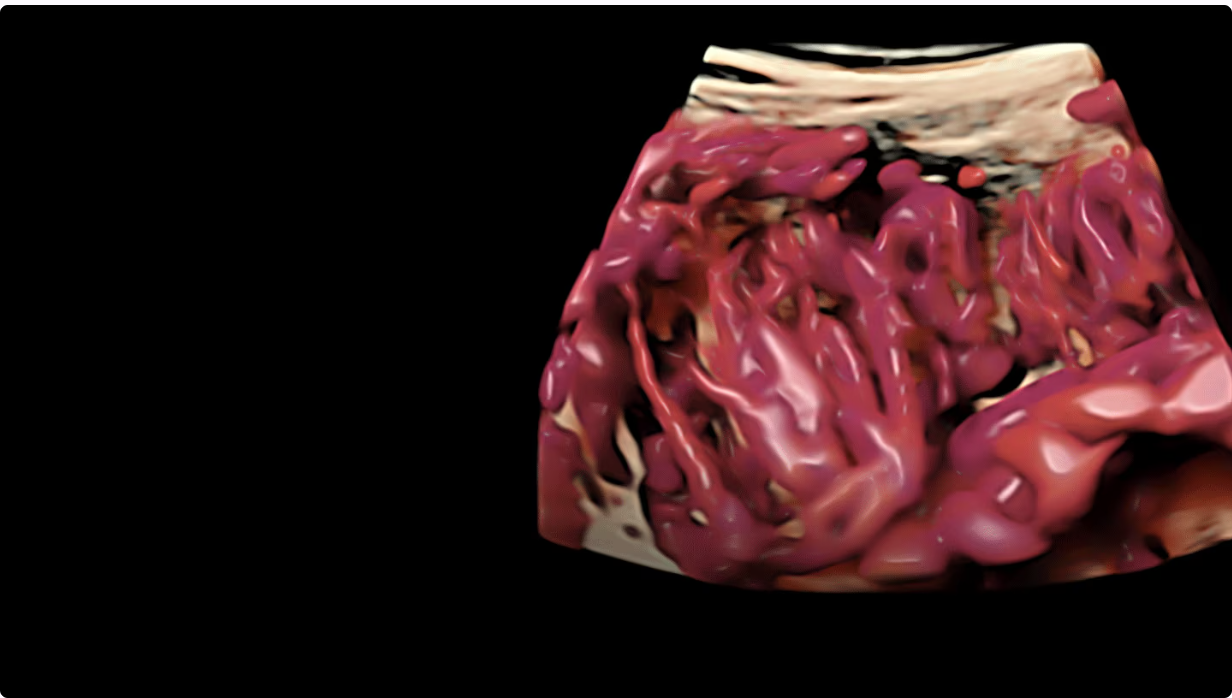

Ультразвуковой аппарат GE Voluson Expert 18 задаёт новый стандарт диагностической визуализации, особенно для сложных акушерских и гинекологических исследований. Созданная на основе усовершенствованной архитектуры Lyric, эта система повышает разрешение и чёткость изображений, обеспечивая превосходные возможности 2D/3D/4D-визуализации для уверенной и точной диагностики. Технология SonoLyst на базе искусственного интеллекта упрощает рутинные исследования, автоматически определяя анатомические особенности плода и оптимизируя измерения, что экономит время и повышает единообразие результатов.

Благодаря таким возможностям, как цветное допплеровское картирование, расширенная объемная визуализация и SonoPelvicFloor, Voluson Expert 18 обеспечивает детальное изображение, имеющее решающее значение для ранней диагностики, вмешательства и клинической уверенности.

С Voluson Expert 18 можно расширить свои возможности и повысить уверенность благодаря превосходному качеству визуализации, основанному на самой передовой архитектуре. Более детальные 2D/3D/4D-изображения и цветное допплеровское картирование для улучшения визуализации в акушерских и гинекологических исследованиях.

- Объемная и допплеровская визуализация: улучшает визуализацию сложных анатомических структур, способствуя точной диагностике.

Объемная визуализация